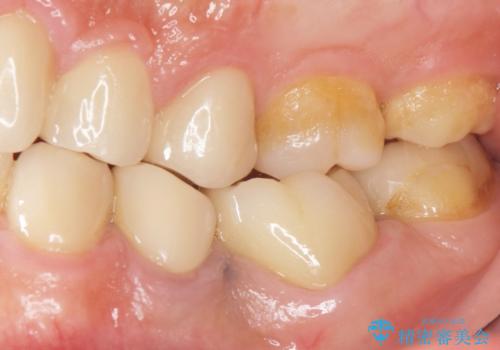

- 奥歯の被せ物をセラミックにしたいとご希望され、来院された患者様です。

左下の奥歯(左下6)の劣化した白い被せ物と金属の土台を除去し、セラミッククラウンによる補綴治療を行いました。

セラミッククラウンの天然歯のような自然な仕上がりと咬み心地に喜んで頂けました。

クラウンの種類:オールセラミッククラウン スタンダード